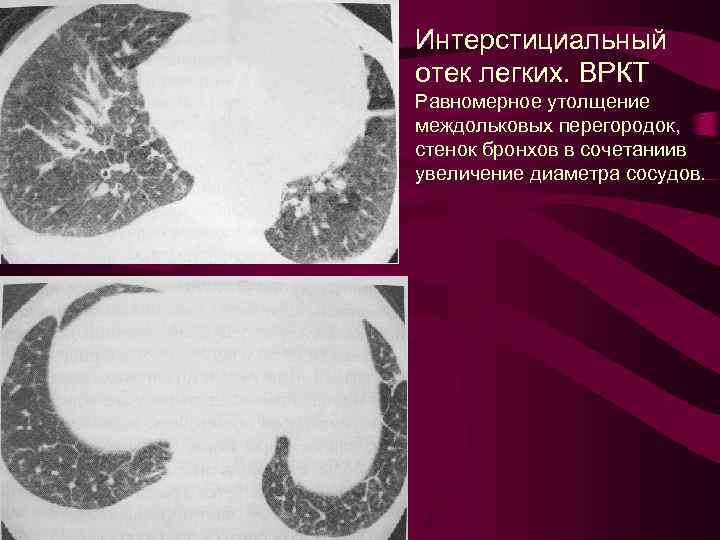

Интерстициальный отек легких. ВРКТ Равномерное утолщение междольковых перегородок, стенок бронхов в сочетаниив увеличение диаметра сосудов.

Интерстициальный отек легких. ВРКТ Равномерное утолщение междольковых перегородок, стенок бронхов в сочетаниив увеличение диаметра сосудов.